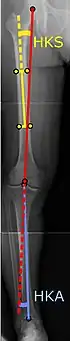

![]() |

Angles commonly measured before knee replacement surgery: |

To indicate knee replacement in case of osteoarthritis, its radiographic classification and severity of symptoms both should be substantial. Such radiography should consist of weightbearing X-rays of both knees: AP, lateral, and 30 degrees of flexion. AP and lateral views may not show joint space narrowing, but the 30-degree flexion view is most sensitive for narrowing. Full-length projections also are used in order to adjust the prosthesis to provide a neutral angle for the distal lower extremity. Two angles used for this purpose are:

- Hip-knee-shaft angle (HKS),[10] an angle formed between a line through the longitudinal axis of the femoral shaft and its mechanical axis, which is a line from the center of the femoral head to the intercondylar notch of the distal femur.[12]

- Hip-knee-ankle angle (HKA),[11] which is an angle between the femoral mechanical axis and the center of the ankle joint.[12] It is normally between 1.0° and 1.5° of varus in adults.[13]